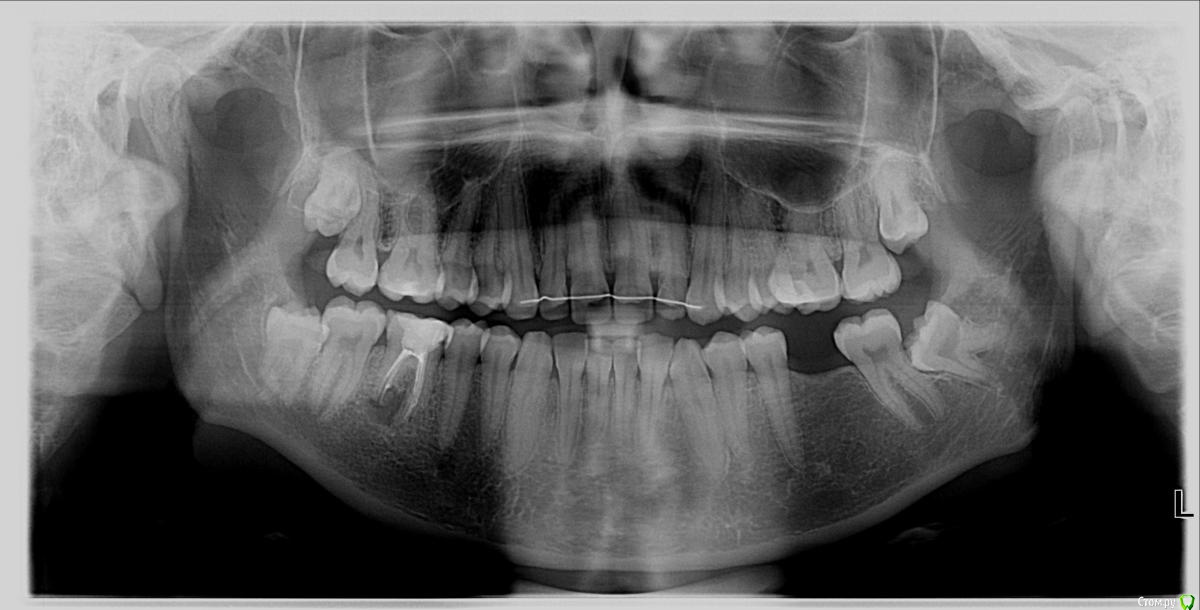

ShallBe Опубликовано 22 ноября, 2016 Поделиться Опубликовано 22 ноября, 2016 Добрый день. Неделю назад удалили 2 зуба мудрости с левой стороны, по показаниям. Врач советует удалять справа тоже, но я не хочу. Они не вылезли и никак не мешают, не "лежат". Врач говорит, что будет неравномерное распределение нагрузки на челюстной сустав, так ли это? Ссылка на комментарий

ShallBe Опубликовано 23 ноября, 2016 Автор Поделиться Опубликовано 23 ноября, 2016 Если жалоб не было, пока бы не трогал. Но это временно, все равно удалять. По какой причине? Челюсть перекосит? Буквально? Если они останутся внутри, то как мне объяснили пойдёт видимая ассиметрия с годами, но на миллиметры. Мне это не принципиально и не пугает. Есть какие-то анатомически важные факторы, чтобы удалить зубы мудрости справа? Могут как-то навредить с точки зрения здоровья? Ссылка на комментарий

Bier Опубликовано 24 ноября, 2016 Поделиться Опубликовано 24 ноября, 2016 самая большая опасность, что 8ка испортит рядом стоящий 7й зуб. 2 Ссылка на комментарий

IvanK Опубликовано 24 ноября, 2016 Поделиться Опубликовано 24 ноября, 2016 самая большая опасность, что 8ка испортит рядом стоящий 7й зуб.+1 что приведет к удалению двух зубов (и 7го и 8го).. 1 Ссылка на комментарий